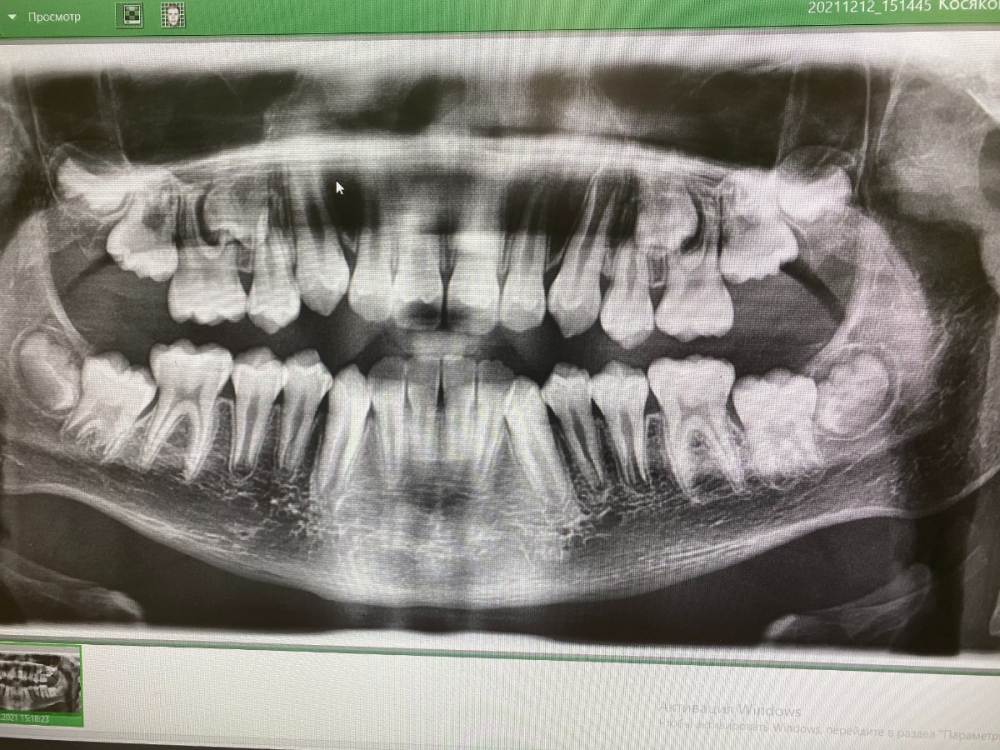

Добрый день! Мальчик 9 лет, все постоянные зубы. Подскажите, пожалуйста, как лучше действовать? Ждать ли пока пятерки прорежутся? До какого возраста? Прорежутся ли они? Сейчас доктор предложил лечение системой Марко Росса на 8 месяцев. Какие могут быть минусы от предложенного варианта? Спасибо большое всем за мнение!

Я бы обратилась к ещё одному ортодонту. Для пятых зубов недостаточно места для прорезывания. Аппарат Марко Роса его не создаст.